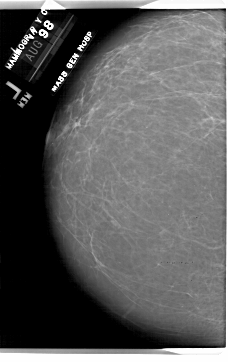

A_1843_1.LEFT_CC

LEFT_CC LINES 6871 PIXELS_PER_LINE 4321 BITS_PER_PIXEL 12 RESOLUTION 43.5 NON_OVERLAY